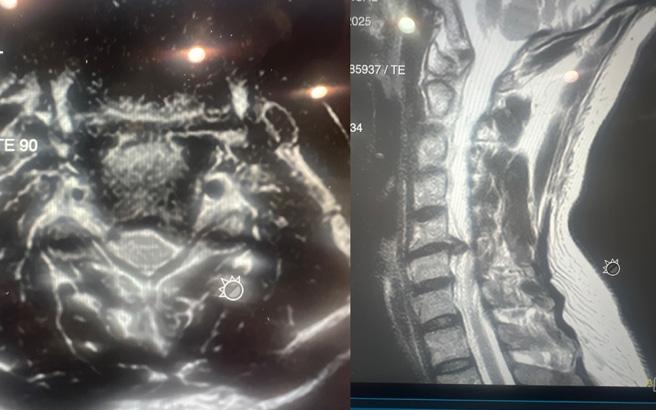

A Long-Term Risk of Cervical Arthroplasty

Cervical disc arthroplasty has emerged as an increasingly adopted alternative to anterior cervical discectomy and fusion. However, unlike fusion, which represents a biological endpoint, arthroplasty introduces a permanent mechanical interface that must remain biologically compatible with host bone for decades. As indications have expanded and younger patients receive these implants, attention has increasingly turned toward the long-term biological interaction between cervical disc prostheses and host bone. One complication that has emerged in longer follow-up studies, yet remains incompletely understood, is periprosthetic osteolysis.

Importantly, several distinct biological processes are often grouped under the term “osteolysis.” Early postoperative bone loss, often seen within the first 3–6 months, represents adaptive remodeling secondary to altered load transfer, endplate vascular disruption, or minor implant micromotion. This phenomenon is typically nonprogressive and clinically silent.1,2 True osteolysis, however, appears to represent a particle-mediated inflammatory process that may emerge years after implantation and demonstrate

progressive bone resorption at the bone–implant interface.

Device-Specific Patterns and Incidence

The incidence of osteolysis following cervical disc arthroplasty appears to vary across implant designs and has been reported to be as high as 64%, likely reflecting differences in bearing surface materials, implant architecture, and load transfer characteristics rather than a single uniform mechanism. 2 Cervical arthroplasty devices can broadly be categorized according to their articulating surfaces, including metal-on-metal, metal-on-polymer, and viscoelastic or polymer-core constructs, each of which introduces distinct wear characteristics that may influence the long-term biologic response of the vertebral body. Greater variability exists when examining individual implants. For example, the M6-C artificial disc manufactured by Orthofix, which utilized an ultra-high-molecular-weight polyethylene core, was associated with a 34% revision rate at an average of 67 months (about 5 and a half years) owing to wear-related osteolysis in one series.7 Reports exist describing polyetheretherketone

(PEEK)-on-ceramic design wear and osteolysis, histologically linked to an inflammatory process. 8 Such analyses have suggested PEEK, titanium, and zirconia debris are linked to inflammatory reactions that may contribute to osteolysis. Metal-on-metal devices have shown radiographic bone loss as high as 52.8%, although most cases are nonprogressive. 9

These findings underscore that osteolysis is not uniform across designs and may reflect differences in bearing materials, fixation strategy, and load transfer. Further, many radiographic changes have gone undiagnosed as patients remain asymptomatic, and there has been inconsistent reporting differentiating osteolysis from other processes such as stress shielding. 9

Clinical Presentation and Diagnostic Challenges

Cervical osteolysis often is asymptomatic early on, thus delaying diagnosis.7,11 Radiographically, osteolysis may present as progressive radiolucent zones surrounding the implant endplates, focal vertebral body cavitation, or erosion extending into the posterior vertebral body. CT often provides superior characterization of bone loss.

Symptomatically, patients may present progressive neck pain or neurologic change related to implant subsidence or device migration. Such delays in diagnosis often lead

to substantial bone loss limiting the ability of revising to another arthroplasty construct and require a fusion with or without a corpectomy.7